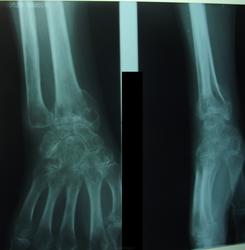

Женщина 1956года, клинически - контрактура лучезапястного сустава, посмотрел на снимок и что - то перемкнуло в голове. Стал задумываться: "А когда имеет рентгенолог право вынести в заключении синдром Зудека?" Коллеги, а есть какие нибудь соображения у вас?